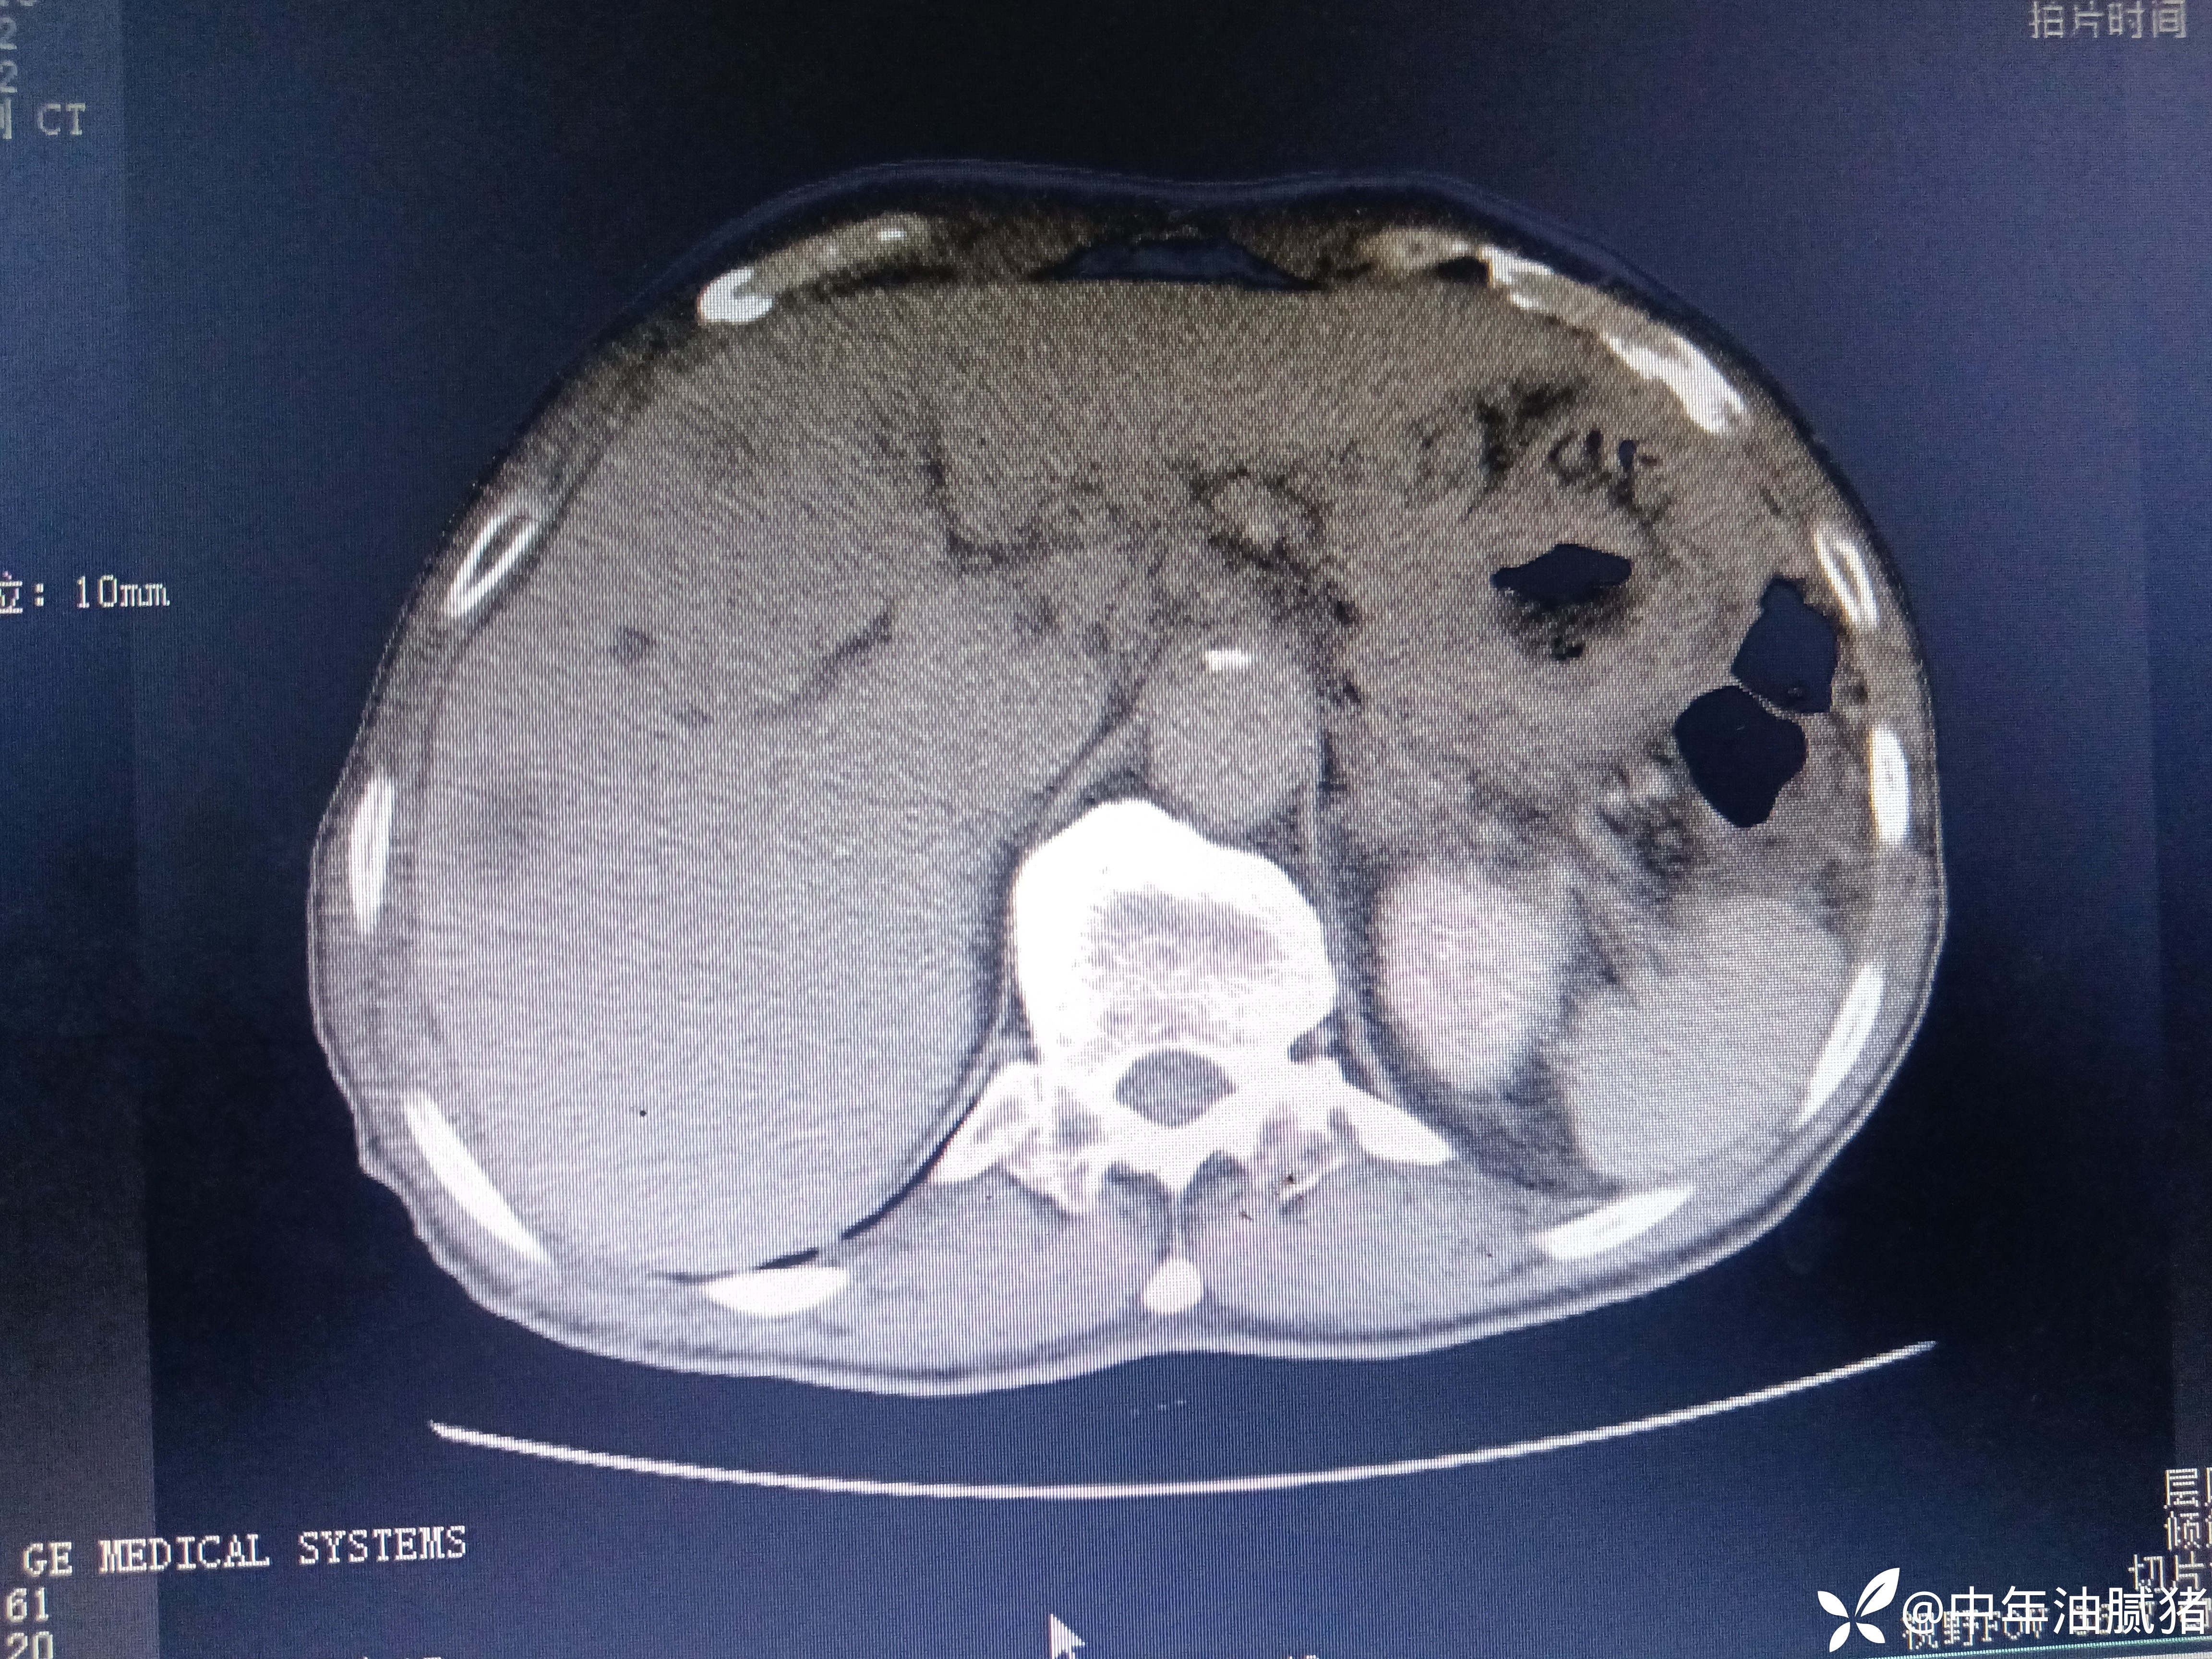

肺ct看到肝内病灶,行增强检查

建议增强ct.报告如下

考虑肝囊肿?让他走?

看后,我隐隐约约觉的不是肝囊肿那么简单?元芳,你怎么看?狄阁老,我也是这么认为!摇人,掏起手机:喂,w主任,请帮我看看这个ct。5分钟后报告修改如下